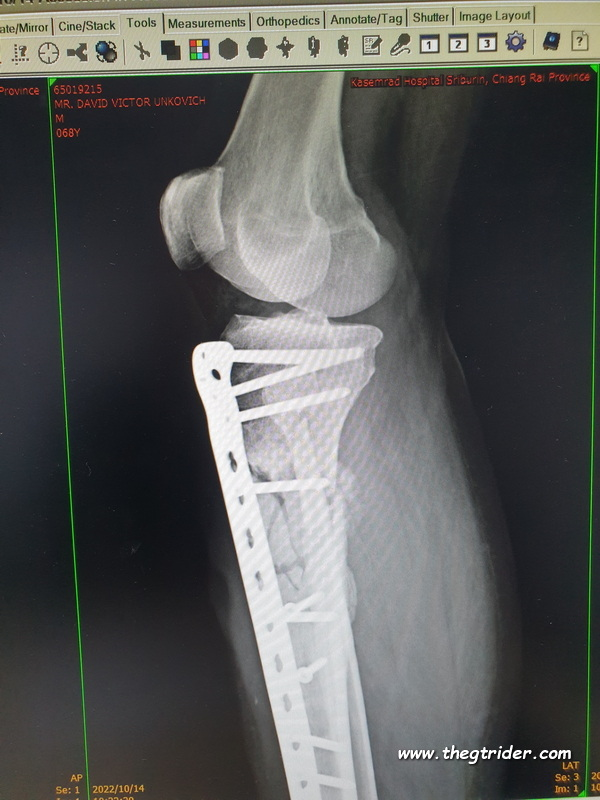

Another brief update, slowly but surely progressing.

My latest check up & xrays, the bones are 80% healed, so I'm allowed to load up the injured leg 50%

Regaining balance & a few strides with crutches is the next "step."

6 more weeks to final check up & al clear for a 100% healed leg & arm, for some real walking & mobility.

The longer it goes on the more frustrating the slog becomes, but I guess I aint doing too bad for an old fellah @ 68.